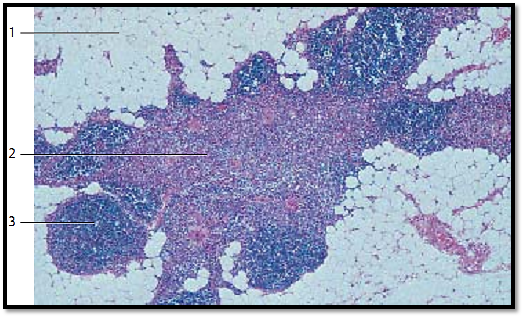

The specific thymus tissue organization slowly disappears in puberty (puberty involution). In the adult thymus, lobules are no longer present. Then the fatty involution ensues (age involution ), which initially affects the cortex more than the medulla. Finally, the residual thymus organ consists mainly of degenerated medullary tissue strands. Note the enormous increase in adipose tissue 1.

1 Adipose tissue

2 Medulla with Hassall corpuscle

3 Residual cortex tissue

Stain: alum hematoxylin-eosin; magnification: × 30